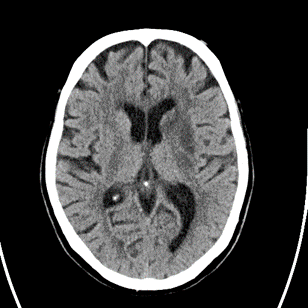

8/ Next evening, patient does the same thing, NIHSS=8, word-๐Ÿฅ—, worsening right hemiparesis. #Strokealert again and CT with new stroke noted. BP at this time 110s:

9/ CTA/P completed as well. LM1 thrombus now appears <occlusive (note that calcification makes vessel appear >open than it actually is), CTP without clear penumbra, but TMax high in posterior MCA division.